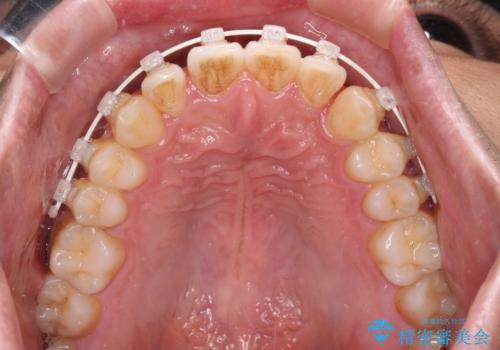

ワイヤー装置での上下前歯の部分矯正

- 矯正装置

- 審美装置

- 1年

- 10-30回

インビザライン廉価版パッケージの方が価格としては安価でしたが、日々の自己管理が煩雑であるとのことで、ワイヤー装置にて矯正治療を行うこととしました。

部分矯正は咬み合わせが不安定になったり、スペースができてしまったりと、適用となる患者様は極めて限られますが、こちらの方はスムーズに治療を終えることができました。